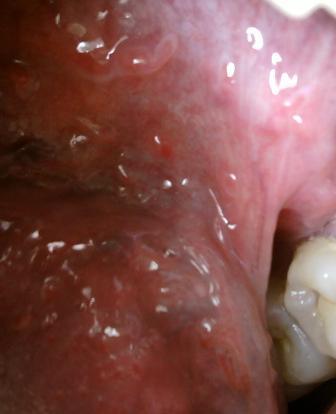

石家庄九州皮肤病医院 > 尖锐湿疣 > > > 石家庄治疗尖锐湿疣医院?对于广大被尖锐湿疣性病困扰的患者来说,及时摆脱病魔是广大患者朋友们最大的心愿,在这里希望广大患者朋友们应该了解,在早期选择一家专业的医院进行诊治对于疾病的治疗和康复是很关键的。

石家庄治疗尖锐湿疣医院?石家庄九洲皮肤病医院是一家治疗尖锐湿疣的权威医院,现在在尖锐湿疣治疗领域已经取得了很优异的成绩,在治疗尖锐湿疣领域有自己独特的优势,患病之后希望广大患者朋友们应该引起重视,切忌不可以耽误治疗,任何疾病初期都是治疗疾病的关键时期,大家不要 因为任何原因而耽误治疗,任何疾病只有经过正规的治疗才能达到理想的治疗效果。